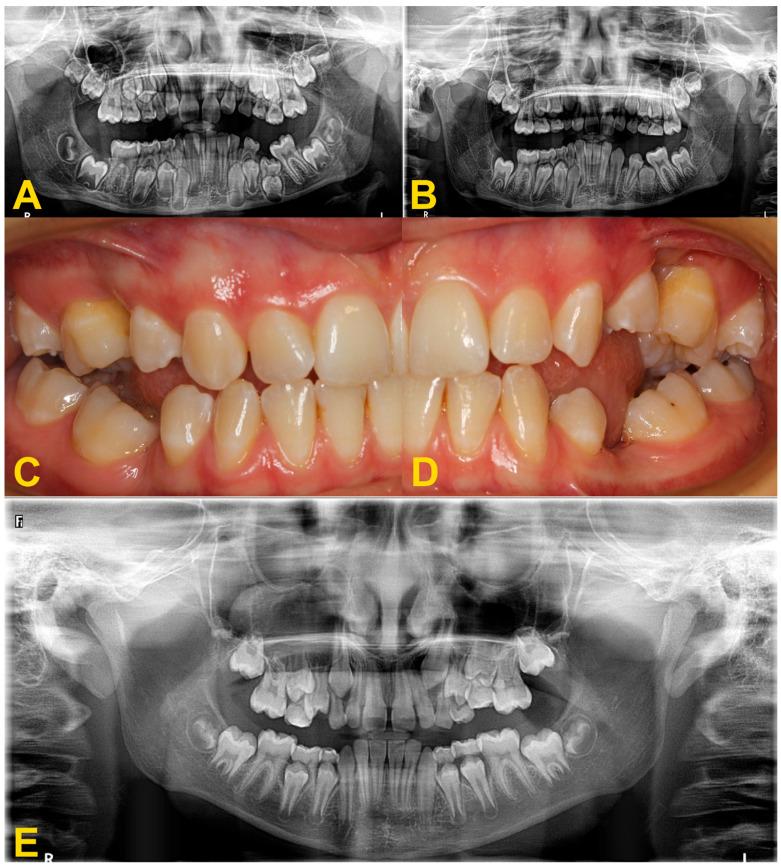

The gradual movement of a tooth away from the occlusal plane is called infraocclusion or reinclusion. Reincluded teeth are most often deciduous molars, and permanent teeth are less frequently affected. Depending on the level of the infraocclusion, the severity of the disorder is classified as mild, moderate, or severe. The etiology of the phenomenon is not fully known. Tooth submerging can lead to serious complications, such as abnormal position of adjacent teeth, displacement of the bud of the permanent successor, shortening of the dental arch, or developmental disturbances of alveolar process. Early diagnosis of the tooth infraocclusion and regular monitoring of its progression help to avoid serious permanent sequelae. The treatment of reinclusion often involves only observation. However, in some cases, the therapeutic procedure requires interdisciplinary treatment by specialists from various fields of dentistry. This study presents current methods of diagnosis and treatment of patients with submerged teeth.

牙齿逐渐离开咬合平面的运动称为低位咬合或再嵌入。再嵌入的牙齿多为乳牙,恒牙则较少受到影响。根据低位咬合的程度,疾病的严重程度分为轻度、中度和重度。该现象的病因尚未完全清楚。牙齿埋没可导致严重并发症,如邻牙位置异常、恒牙胚萌出受阻、牙弓缩短或牙槽骨发育障碍。早期诊断牙齿低位咬合并定期监测其进展有助于避免严重的永久性后遗症。再嵌入的治疗通常仅涉及观察。然而,在某些情况下,治疗过程需要由来自不同牙科领域的专家进行跨学科治疗。本研究介绍了目前诊断和治疗埋藏牙患者的方法。